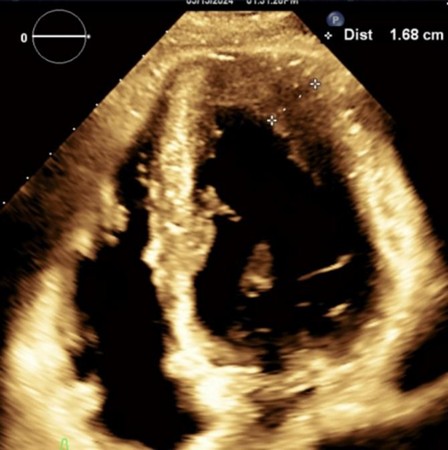

Figure 3. Transthoracic Echocardiogram, 2 chamber parasternal short axis view, demonstrating apical hypertrophy. The left ventricular wall measured 1.68 cm, greater than 15 mm, coinciding with the diagnosis of hypertrophic cardiomyopathy.